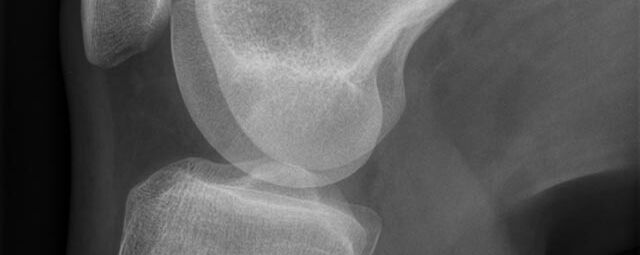

Röntgen Knochen

• Fraktur

• Arthrose

• Rheumatische Gelenkerkrankungen

• Degenerative Veränderungen der Wirbelsäule

• Knochentumor

• Osteoporose

• Therapiekontrolle nach OP am Skelettsystem

• Vollautomatische Erstellung von Ganzbein- und Ganzwirbelsäulenaufnahmen